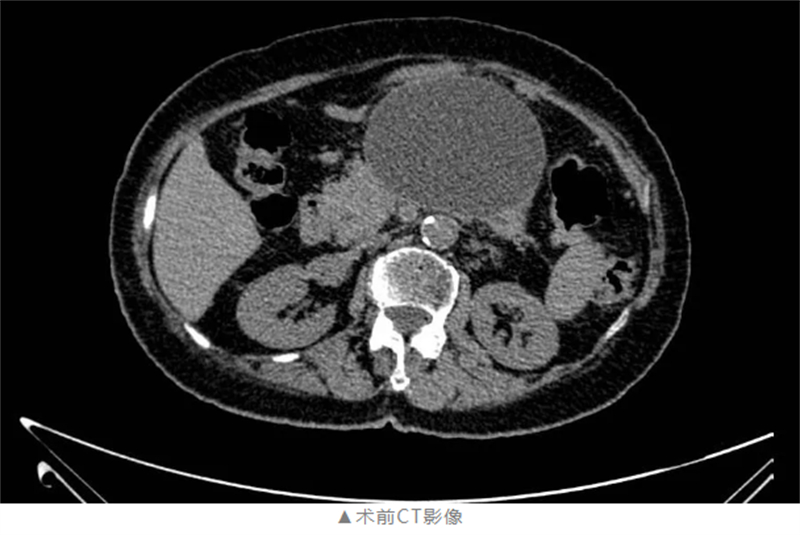

69歲的高女士(化名)在過(guò)去的一個(gè)月里,反復(fù)遭受嘔吐胃內(nèi)容物和腹脹的折磨。在當(dāng)?shù)蒯t(yī)院就診后,腹部CT檢查提示她患有“胰腺假性囊腫”,雖經(jīng)多次治療但效果不佳。隨著嘔吐頻率的增加,高女士的營(yíng)養(yǎng)攝入受到嚴(yán)重阻礙,日常生活幾乎陷入癱瘓。面對(duì)病痛的折磨,高女士懷揣著對(duì)健康的渴望,來(lái)到了柳州市人民醫(yī)院肝膽胰疾病門診。

手術(shù)如期進(jìn)行,在麻醉科團(tuán)隊(duì)的密切配合下,消化病肝膽胰疾病診療中心手術(shù)團(tuán)隊(duì)嫻熟地操作超聲內(nèi)鏡,準(zhǔn)確定位囊腫位置,避開(kāi)重要血管和器官,成功完成穿刺引流并植入支架。整個(gè)手術(shù)過(guò)程僅耗時(shí)約40分鐘,術(shù)中無(wú)出血,展現(xiàn)了柳州市人民醫(yī)院醫(yī)療團(tuán)隊(duì)高超的技術(shù)水平和專業(yè)素養(yǎng)。

此次手術(shù)的成功實(shí)施,不僅為高女士解除了病痛,更標(biāo)志著醫(yī)院在肝膽胰疾病微創(chuàng)治療領(lǐng)域取得了新的突破。術(shù)后第一天,高女士即可下床活動(dòng),腹脹癥狀明顯緩解,能夠正常進(jìn)食。復(fù)查顯示囊腫明顯縮小,引流效果良好。高女士激動(dòng)地說(shuō):“真沒(méi)想到恢復(fù)得這么快!之前嘔吐得厲害,現(xiàn)在終于能好好吃飯了。”